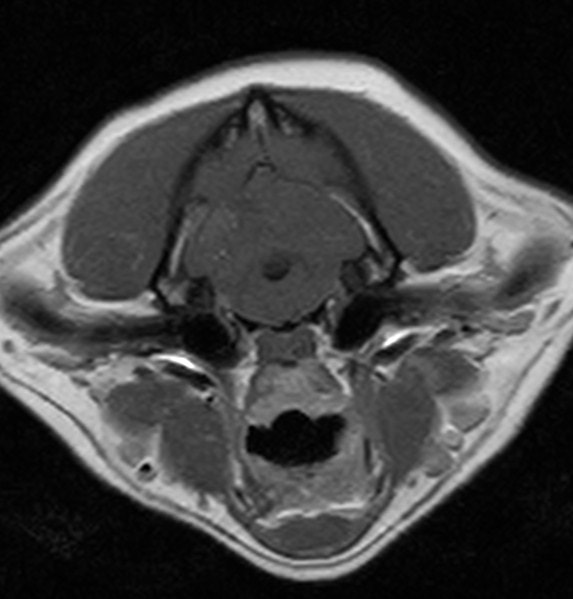

変性性脊髄症と椎間板ヘルニアを併発したウェルシュコーギーの脊髄MRIです。椎間板物質の脊髄への圧迫像がみられます。しかし、MRIだけでは後肢の麻痺がこの椎間板の突出に由来するのか、変性性脊髄症に由来するのかの見分けはつきません。